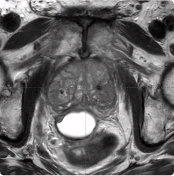

BioProtect 215cc Prostate

215 cc Prostate Post-MRI showing BioProtect Balloon Spacer, prostate, and rectum.

Post-MRI

Image courtesy of Dr. Shawn Zimberg, Radiation Oncologist.